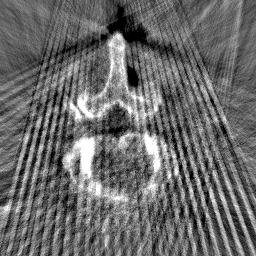

Disentanglement and explicit shape constraints. As shown in Fig. 4, we can see streak metal artifacts nearly everywhere in . M1 can roughly disentangle artifacts and anatomical information but strong vertical artifacts and strange air area appear in (see red arrows of M1 in Fig. 4). For the anatomical structure, M1 learns to segment vertebrae with fully supervised and applied on various CT images, but fails to suppress the false bony structure in and as may misclassify some metal artifacts as bone.

Implicit shape constraints. With , all segmentations are improved with higher Dices and smaller ASDs, see Table 1. As shown in Fig. 4, , and become similar but the high density bone is not correctly segmented in as it maybe treated as metal artifacts. Comparing between M2 and M1, the abnormal air region disappears but metal artifact reduction performance is still not satisfactory.

Anatomy-aware generation. With AADE layer in M3, , and are substantially improved as shown in Table 1. Note, is used as attention map, so we do not expect it to be identical to . In , metal artifacts are further suppressed comparing with M2. Thus, AADE is critical to our anatomy-aware artifact disentanglement framework. With the special structure, can be punished in the image translation and reconstruction processes and the other encoders and generators receive more guidance. However, as shown by blue arrows in Fig. 4, we observe a shadow of vertebra edge of appears in of M3 and the vertebra boundaries get smoothed out in . It may be because sharp edges are encoded as metal artifacts and forced to be added to by artifact consistency loss .

Removal of . To mitigate vertebrae shadows, we remove . The segmentation performance of most images in M4 gets improved because of better synthetic images. Overall, in M4 yields the best segmentation performance for CBCT images with an average Dice of 0.847 and an average ASD of 1.54 mm. For the synthetic images, M4 generates with the best quality and least metal artifacts among all the models. M4 also outputs without vertebra shadows. The results indicate our shape-aware network could preserve anatomical details and transfer the metal artifacts precisely without .